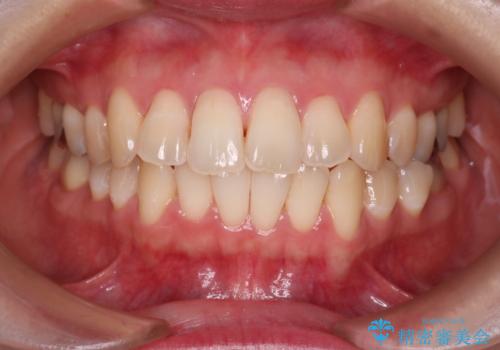

- 前歯のガタガタを主訴に来院された患者様です。

前歯の傾きも少し内側に入るように計画をたて、インビザラインにて治療を行いました。

このぐらいのガタガタであれば、インビザラインで簡単に治すことができます。